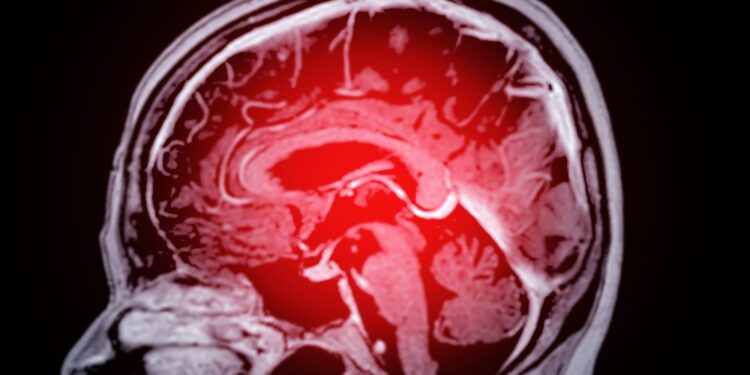

Pagrindinės diagnostikos priemonės

Įtariant kraujavimo insultą taikomi įvairūs tyrimai, leidžiantys įvertinti smegenų būklę ir nustatyti pažeidimo mastą. Dažniausiai atliekama:

- Kompiuterinė tomografija (KT)

- Magnetinio rezonanso tomografija (MRT)